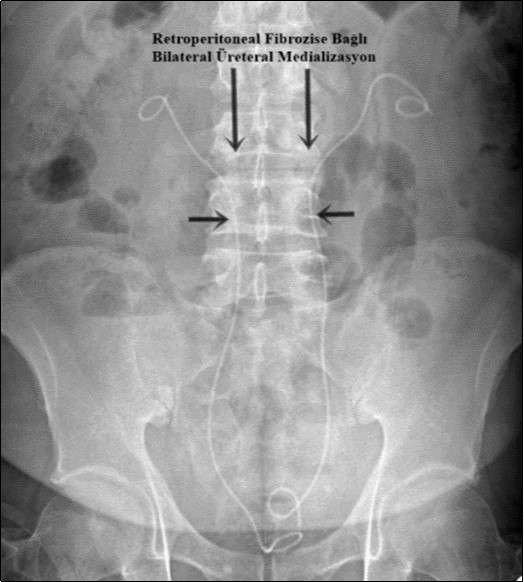

A 58-year-old male patient was admitted to our clinic with complaints of severe weakness, loss of appetite and decreased urine volume. The patient had chronic, mild lower urinary tract symptoms. Serum creatinine level of the patient was 5.3 mg/dl and he had no additional diseases except hypertension. Bilateral grade 3 hydronephrosis and moderate residual urine was revealed in urinary ultrasonography. A transurethral foley catheter was inserted and the patient was admitted to the internal medicine intensive care unit with the diagnosis of acute renal failure due to infravesical obstruction. During follow-up, abdominal magnetic resonance imaging (MRI) was performed due to oliguria and high serum creatinine level (Figure 1). Magnetic resonance imaging revealed a mass of approximately 88x49 mm in the axial plane at the renal artery outlet level, consistent with retroperitoneal fibrosis, tuberculous lymphadenitis or lymphoma. Grade 3 pelvicaliectasis was seen in bilateral kidneys. The descripted lesion was observed in paraaortic area (except posterior). Tru-cut biopsy was planned with no evidence of malignancy on positron emission tomography. Tru-cut biopsy reported as connective tissue. Bilateral double-J ureteral stent was placed endoscopically to patient who was diagnosed as idiopathic retroperitoneal fibrosis (Figure 2). At the same time, alpha-blocker treatment was started. Creatinine levels decreased to normal after five days and normal volume voiding was observed after removal of foley catheter. The patient was started on glucocorticoid therapy which was foreseen to last for 1 year. After 2 months, PET imaging showed the decreased mass size and metabolic activity. Thereafter bilateral ureteral double-J stents were removed endoscopically. Ultrasonographic imaging showed no hydronephrosis after 7 days of catheter removal and the patient was recommended to continue glucocorticoid therapy and was followed up.

Figure 2.Ureteral diversion with bilateral double-J catheter. Both ureters were pulled medially due to retroperitoneal fibrosis.